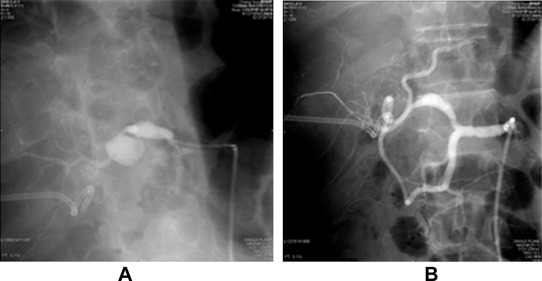

A 65-year-old male had recurrent hepatocellular carcinoma and underwent living donor liver transplantation in 2011. On the 8th postoperative day, the patient underwent re-exploration due to a significant drop in hemoglobin level despite blood transfusion. Diffuse oozing was noted around the celiac trunk. Hemostasis materials were applied, and the bleeding was controlled. The patient had to be re-explored again 7 days later due to persistence of bleeding that revealed active bleeding from hepatic artery anastomosis. The bleeding was sealed off with hemostasis materials. The patient was subjected to celiac angiography due to persistent drop in hemoglobin level. The angiographic results revealed pseudoaneurysms in the left gastric artery and hepatic artery anastomosis. Left gastric artery pseudoaneurysm was successfully occluded with coil embolization. An endovascular stent graft (Jostent, Abbott Vasculat Inc. Santa Clara, CA, USA, 4 mm/16 mm) was placed and hepatic artery pseudoaneurysm was excluded (Fig. 3). Postprocedure angiography showed adequate flow in the liver graft. Bacterial cultures for blood, sputum, and urine were performed and only sputum culture showed S. maltophilia growth. The patient recovered well and was discharged 2 weeks later. The patient is doing well and regularly followed up.

Hepatic artery angiography for Case 3. (A) Pseudoaneurysm at the anastomotic ...

Figure 3.

Hepatic artery angiography for Case 3. (A) Pseudoaneurysm at the anastomotic site and the left gastric artery. (B) Pseudoaneurysm disappeared after placement of stent graft. The left gastric artery was embolized by coil.